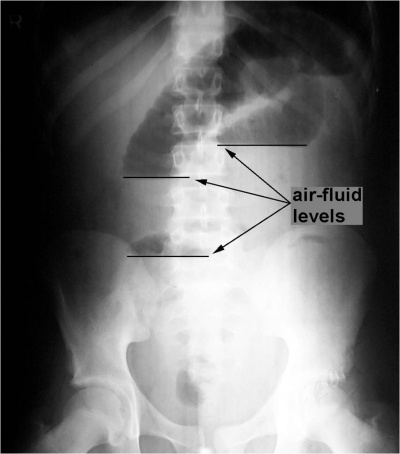

בצילום בטן סקירה ניתן לראות חסימות דינמיות, התרחבות של המעי הדק (תצלום 1.4), ופלסי אוויר נוזל במרכז הבטן המסודרים בצורת מדרגות (תצלום 2.4). הוולבולה קוניובנטס מודגשים לרוחב הרירית (תצלום 3.4).

בחסימות של המעי הדק לא תהיה עדות לאוויר בכרכשת (תצלום 4.4 - 5.4). בצילום צדדי של החלחולת לא ניתן לראות אוויר בחלחולת. לעומת זאת, בחסימות של הכרכשת יש הרחבה של הכרכשת והדגשה של ההאוסטרות בהיקף הבטן. בחולים שאובחנה בהם חסימה של הכרכשת, שבהם מסתם אילאוצקלי בלתי פעיל, תיראה הרחבה של הכרכשת והמעי הדק.